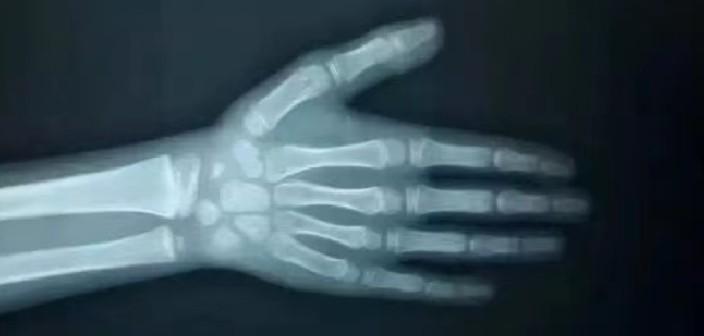

青春期孩子可半年测一次骨龄

要特别提醒的是,骨龄决定了孩子的生长空间和潜力,当骨龄和年龄有可能存在严重偏差,这种情况下只按照年龄来判断孩子的身高是偏离实际的,建议家长每年带孩子测一次骨龄,对于青春期的孩子,如有需要的话,可以半年测一次骨龄。

义诊福利:免费拍摄骨龄片(采用先进AI骨龄仪);为前25名报名并且符合矮小标准儿童提供现场免费专家义诊号,与专家一对一咨询;免费领取生长发育干货礼包(包括生长发育科普三折页等等长高工具,干货满满,数量有限、先到先得);免费获得孩子专属的生长发育评估报告。